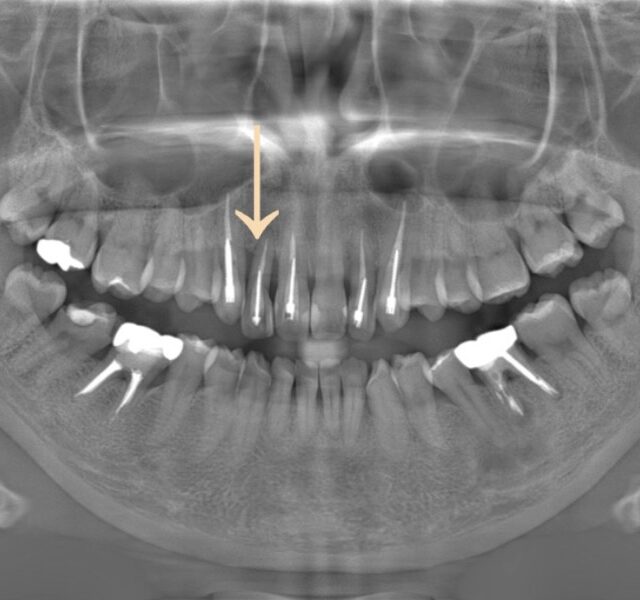

自分でインプラントを入れてみた感想③ 2021年9月30日 院長blog こんばんは。院長の粟谷です。 私自身のブログの更新は1年以上空いてしまいました。 ちょうど明日でグランツがオープンしてから2年が経過します。 たくさんの患者さんに来ていただき、本当にありがたいことだなと感謝の気持ちでいっ… 続きを読む